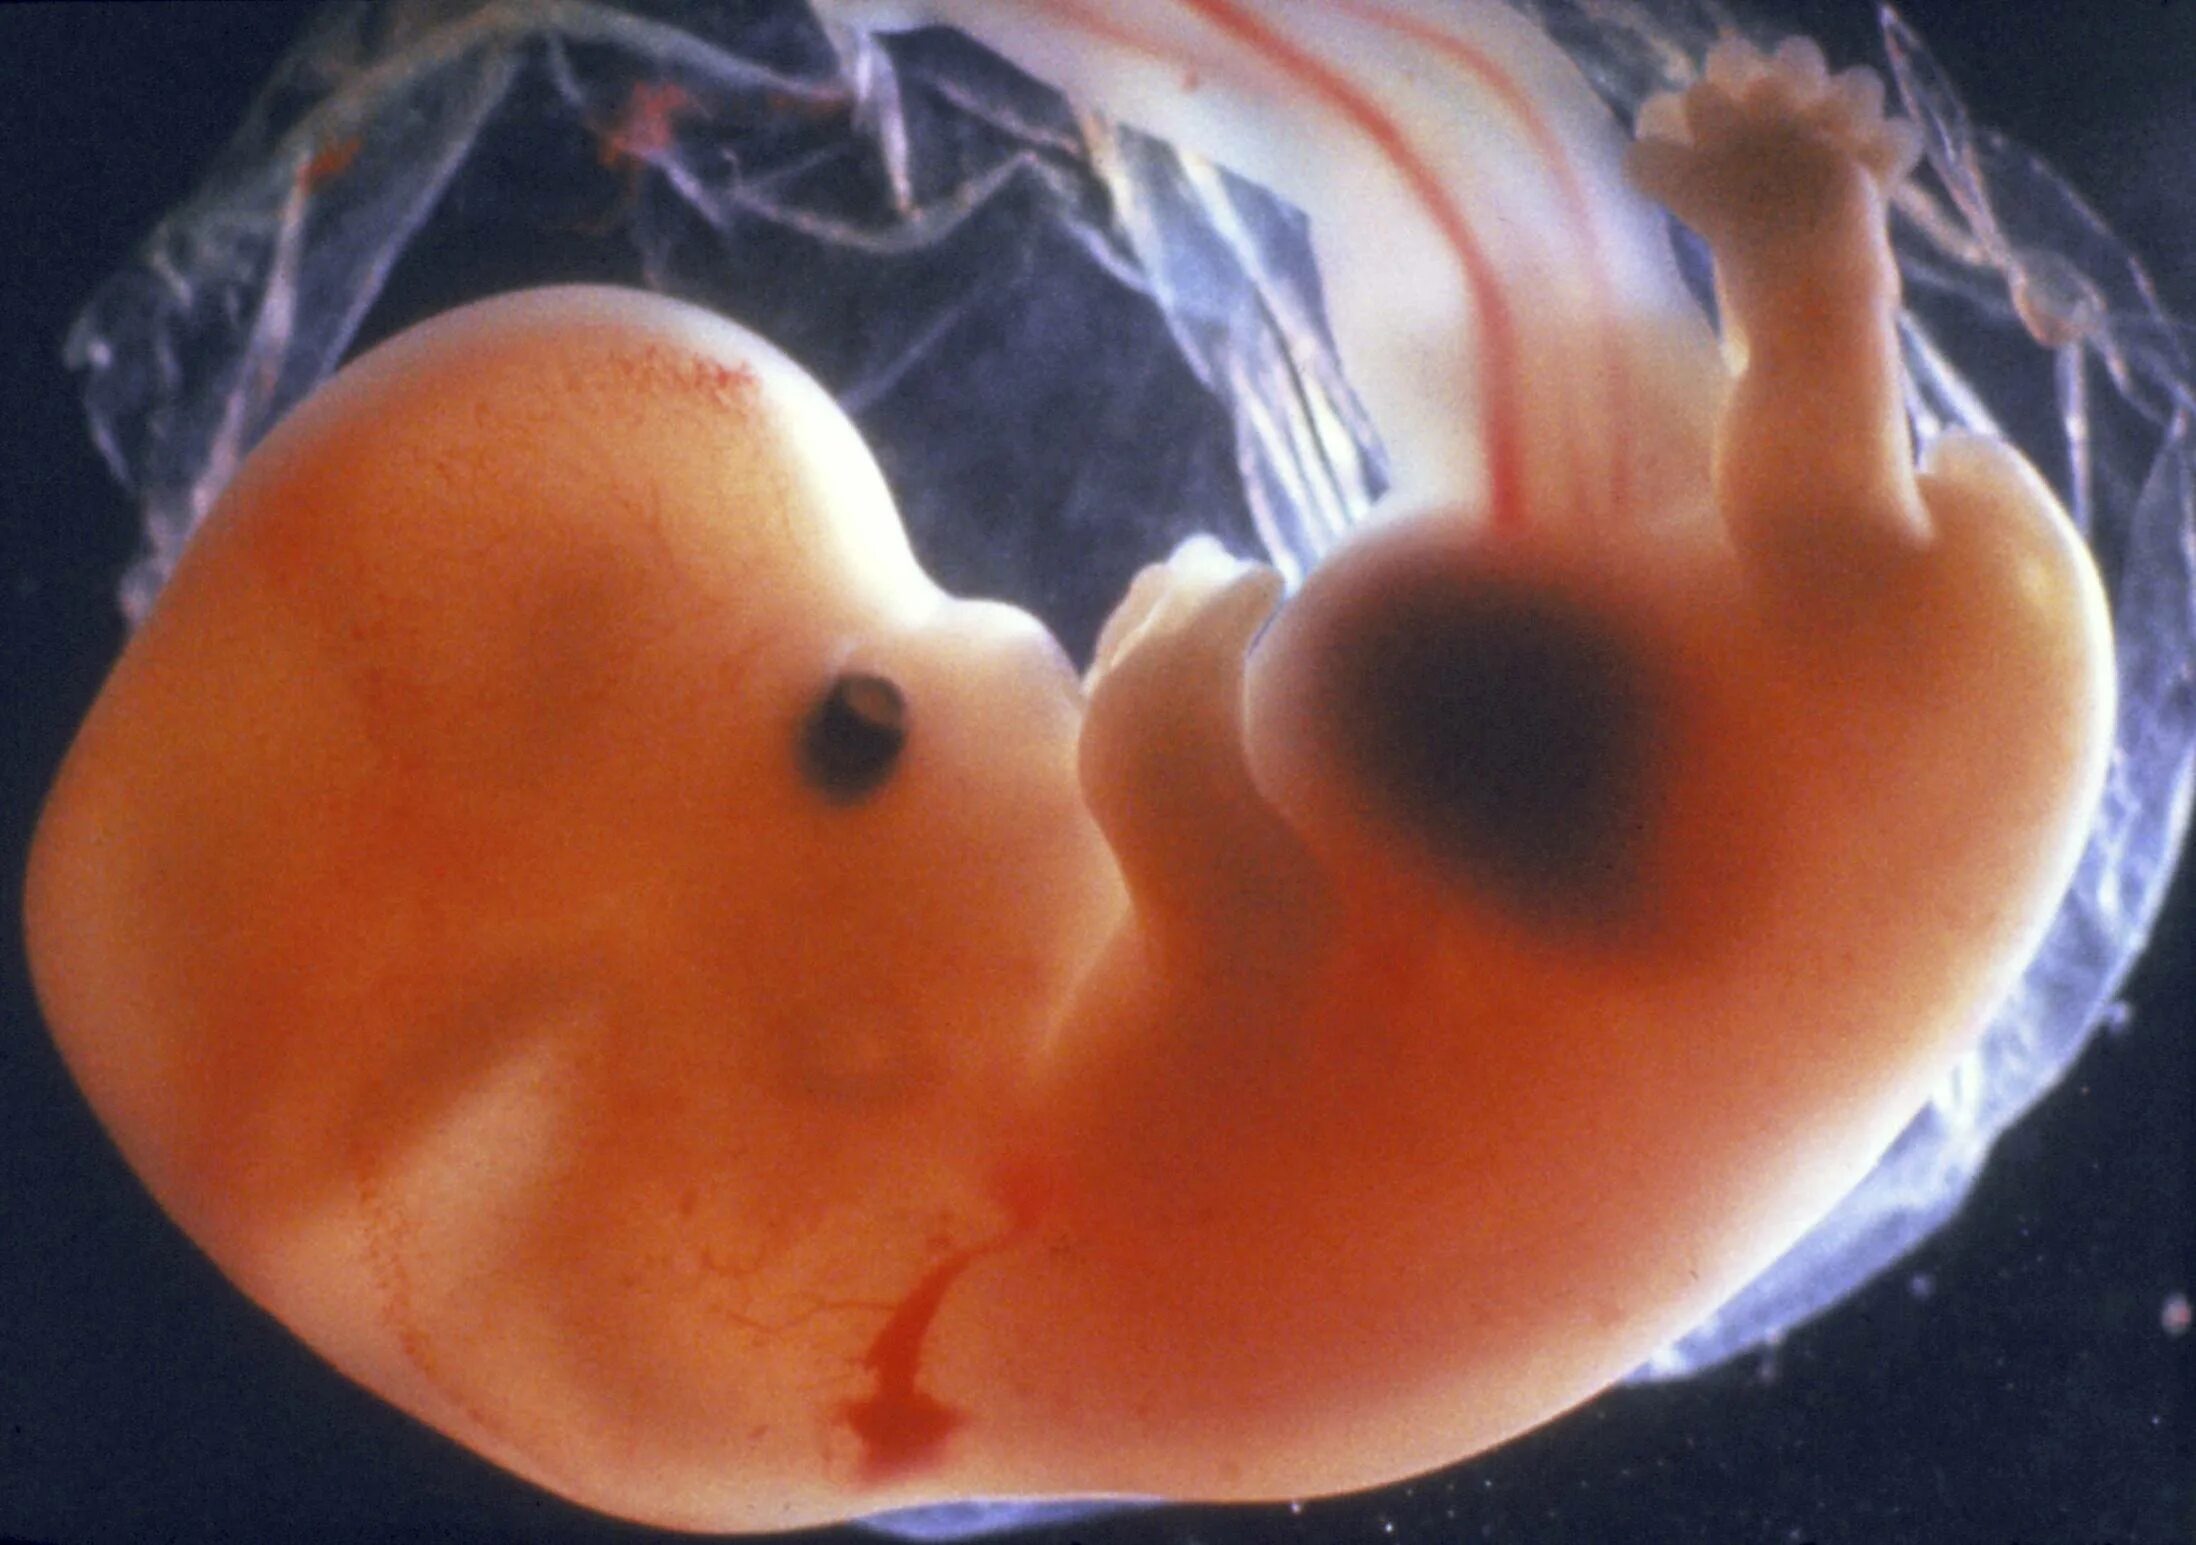

Как выглядит 5 дней беременности